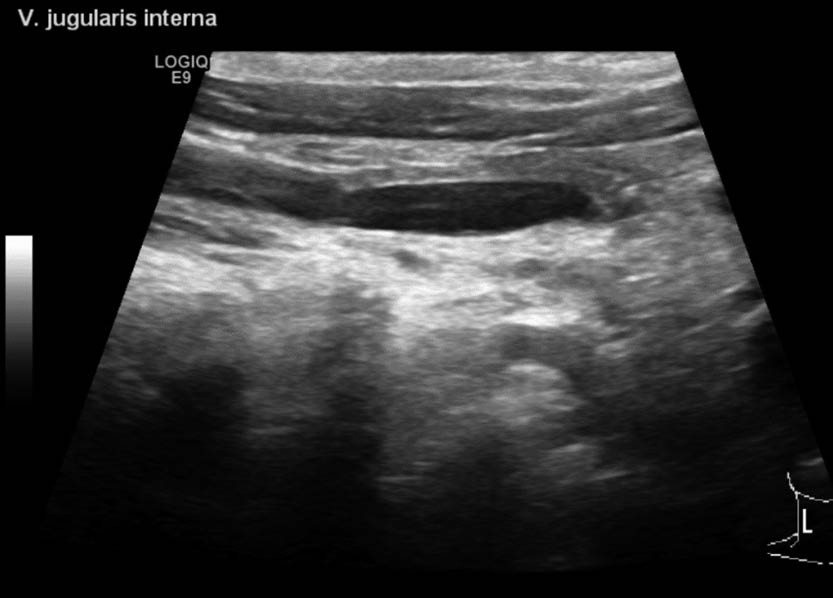

Aufgrund der symptomatischen Cholezystolithiasis nach stattgehabter akuter Cholezystitis wurde die Indikation zur elektiven laparoskopischen Cholezystektomie gestellt. An diagnostischen Verfahren wurden auswärts ein Angio-MRT (Abb. 1 – 4) des Oberbauches und eine Magnetresonanz-Cholangiopankreatikographie (MRCP) durchgeführt, welche eine Cholezystitis bei Cholezystolithiasis und eine beginnende Leberzirrhose nachweisen konnten. Im Rahmen der präoperativen Vorbereitung wurde eine Echokardiographie durchgeführt, in welchem eine Herzinsuffizienz infolge der Volumenbelastung durch die AV-Shunts i.R. des KMS und eine „Cirrhose cardiaque“ ausgeschlossen werden konnten. Als Marker einer intravasalen Gerinnungsaktivierung wurden erhöhte Prothrombinfragmente, D-Dimere und eine erniedrigte Antiplasmin-Konzentration sowie eine gesteigerte Fibrinolysekapazität detektiert. Eine sekundäre Thrombozytopenie oder eine Fibrinogen- und Faktor-XIII-Verminderung konnten ebenso wie das Vorliegen eines erworbenen von-Willebrand-Syndroms ausgeschlossen werden.

In einer hämostaseologischen Vorstellung wurde die Pausierung der Thrombozytenaggregationshemmung über 7 d unter „Bridging“ mittels niedermolekularem Heparin und eine medikamentöse Hemmung der Hyperfibrinolyse durch Tranexamsäure bis zum 3. postoperativen Tag bzw. in Abhängigkeit von Klinik und des hämostaseologischen perioperativen Monitorings empfohlen. Als perioperative Antibiotikaprophylaxe wurde Imipenem eingesetzt. Der Kameratrokar wurde entsprechend der aus dem Angio-MRT bekannten linksseitigen Ausprägung der Gefäßmalformationen (Abb. 1 – 4) in typischer Nabelposition platziert.

Unter diaphanoskopischer Kontrolle (Abb. 5) mussten die 2 weiteren epigastrischen Arbeitstrokare etwas mehr rechtsseitig positioniert werden. Intraoperativ (Abb. 6) stellte sich die Gallenblase sowohl akut als auch chronisch entzündlich verändert dar. Die Leber zeigte makroskopisch venöse Malformationen sowie einen beginnend kleinknotigen Parenchymumbau. Die laparoskopische Cholezystektomie verlief ohne Komplikationen, auf die Einlage von lokalem Drainagematerial konnte verzichtet werden. Die pathohistologische Aufarbeitung (Abb. 7) zeigte eine chronisch-fibrosierende Cholezystitis mit Gallenblasenwandverdickung ohne Anhalt für Malignität.